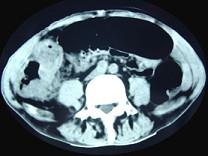

问题 男,70岁,右下腹胀,腹痛,腹泻,影像检查如图,最可能的诊断是 ( )

选项 A、结肠结核 B、结肠淋巴瘤 C、结肠癌 D、结肠套叠 E、结肠克隆恩病

答案 C